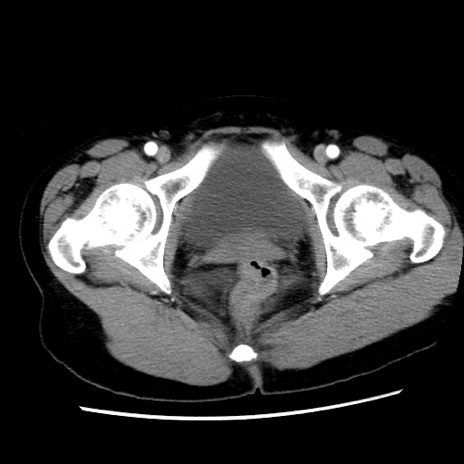

症例10(横断像)

【症例】 50歳代女性

【主訴】 腹痛

【現病歴】前日生レバーを食べた。今朝に排便あり。 昼前に突然発症の腹痛を生じ、当院救急外来を受診した。

【既往歴】 子宮筋腫にてで子宮全摘後

【身体所見】 意識清明、腹部:平坦、軟、下腹部やや左を中心に圧痛・反跳痛あり、筋性防御あり

【データ】WBC 7800、CRP 0.07